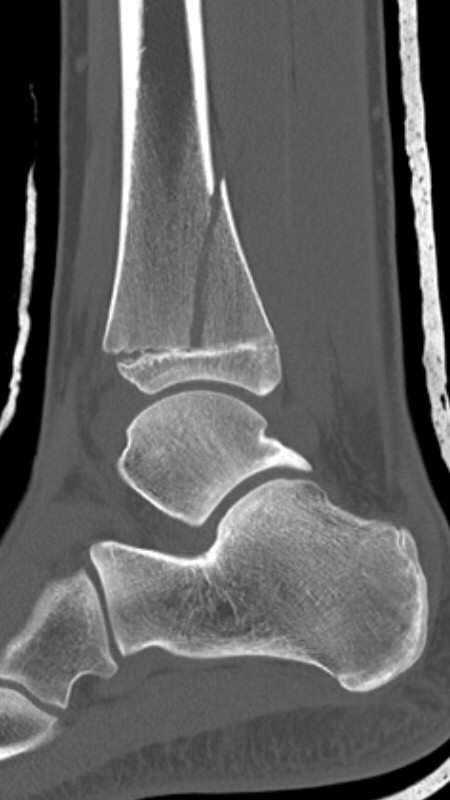

Distal tibiafyseolys SH 4 triplansfraktur (barn)

Triplanfraktur = triplansfraktur = treplansfraktur: fraktur i distala tibia som engagerar både metafys, fys och epifys. Kan vara 2, 3 eller 4 fragment. I 50 % av fallen är även fibula frakturerad [3].

Exempel på triplansfraktur hos nästan färdigvuxet barn

På akutmottagning

Gör DT för att avgöra frakturtyp och felställning.